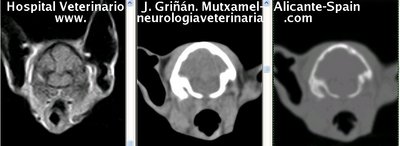

Se muestran cortes transversales de Resonancia Magnética (imagen a la izqda del lector), TC contrastado para tejidos blandos (imagen del centro) y TC contrastado para tejidos duros (imagen de la derecha del lector).

Nótese como la Resonancia supera al TC en el contraste de tejidos blandos (encéfalo y médula espinal) y en el de líquidos (ojo y líquido cefalorraquídeo), mientras que el TC supera a la resonancia en el contraste de tejidos duros (hueso) y aire (senos, cavidad nasal y bullas)

Cortes a nivel de los lóbulos cerebrales frontales